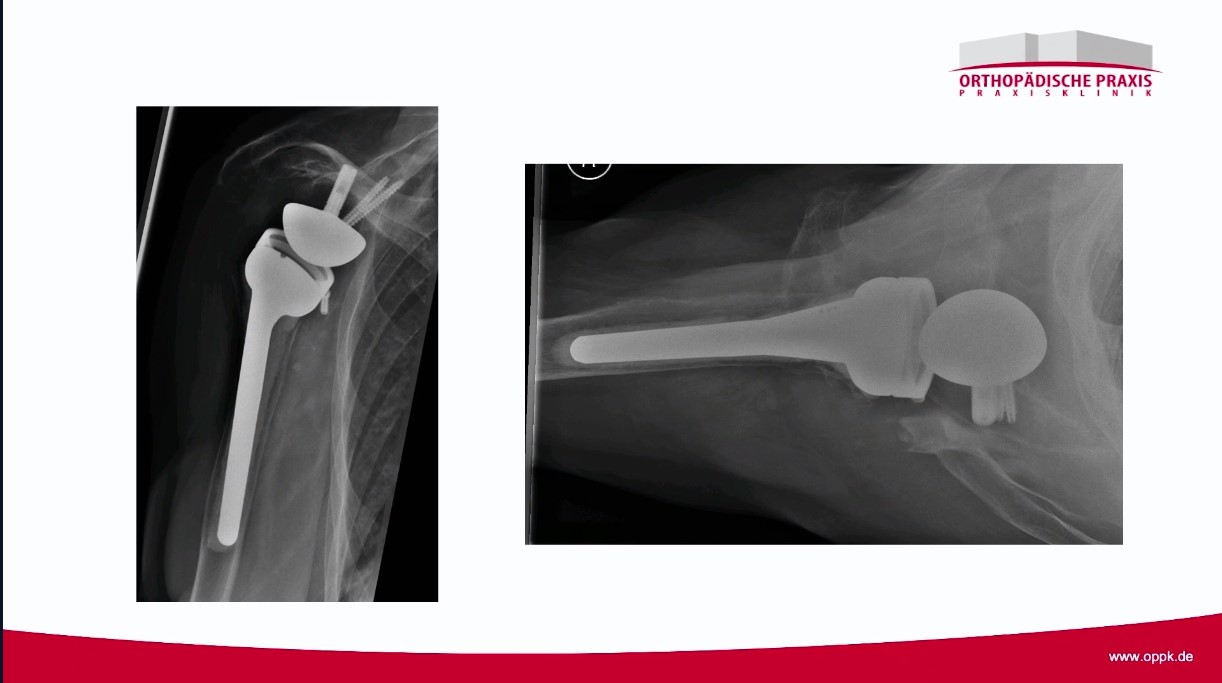

Winglet Originals #028: Complex Humerus Fractures

Winglet Originals TV Series «The Cutting Edge»

Winglet Originals #021: Reverse Shoulder Arthroplasty – thumbnail 1 of 11 Winglet Originals #021: Reverse Shoulder Arthroplasty – thumbnail 2 of 11 Winglet Originals #021: Reverse Shoulder Arthroplasty – thumbnail 3 of 11 Winglet Originals #021: Reverse Shoulder Arthroplasty – thumbnail 4 of 11 Winglet Originals #021: Reverse Shoulder Arthroplasty – thumbnail 5 of 11 Winglet Originals #021: Reverse Shoulder Arthroplasty – thumbnail 6 of 11 Winglet Originals #021: Reverse Shoulder Arthroplasty – thumbnail 7 of 11 Winglet Originals #021: Reverse Shoulder Arthroplasty – thumbnail 8 of 11 Winglet Originals #021: Reverse Shoulder Arthroplasty – thumbnail 9 of 11 Winglet Originals #021: Reverse Shoulder Arthroplasty – thumbnail 10 of 11 Winglet Originals #021: Reverse Shoulder Arthroplasty – thumbnail 11 of 11

Winglet Originals #021: Reverse Shoulder Arthroplasty

Winglet Originals TV Series «All About Techniques»